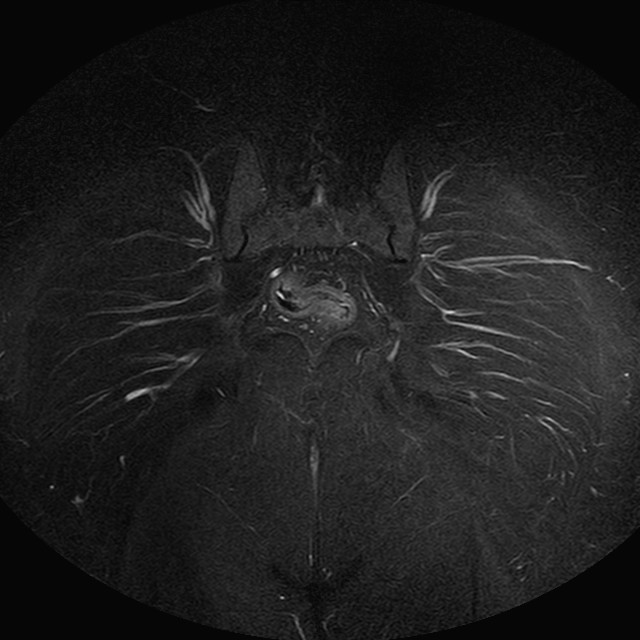

Esami: RMN BACINO

eSTIR

Evidenti e simmetriche alterazioni osteofitosiche in regione coxo femorale con riduzione delle rime articolari. Degenerazione completa del cercine glenoideo. Non attuali segni di versamento articolare. Non segni di edema osseo che escludono attuale algodistrofia od osteonecrosi. Lieve e simmetrica riduzione del trofismo della muscolatura glutea.